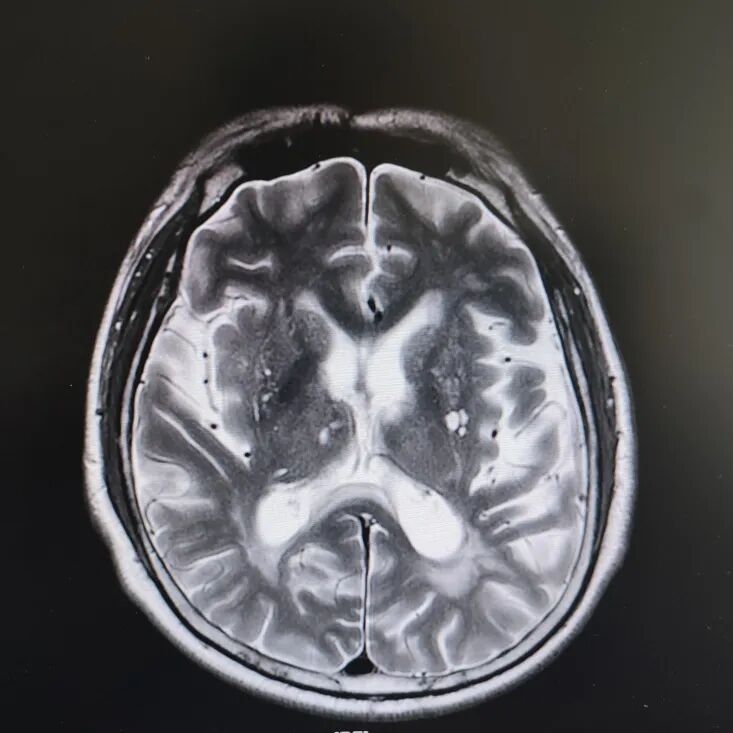

病房里還有另一位患者,來的時候情況更讓人揪心:反應遲鈍,表情呆滯,行動緩慢。頭顱核磁顯示腦萎縮明顯,但查體發(fā)現肌張力、計算力、記憶力、定向力均正常,不符合典型血管性癡呆或阿爾茨海默病表現。

患者頭部磁共振影像

憑著多年診治疑難雜癥的豐富經驗,趙主任敏銳地意識到這“癡呆”可能是假象,背后另有隱情。他果斷建議進一步做特殊感染篩查。果然,檢查證實這位患者同樣是感染了蒼白密螺旋體!經過精準的抗感染治療,奇跡發(fā)生了:患者的反應變快了,眼神靈活了,走路也恢復了正常步態(tài)。最終的診斷是“麻痹性癡呆”——一種由神經梅毒引起的、可治療逆轉的“癡呆”類型!